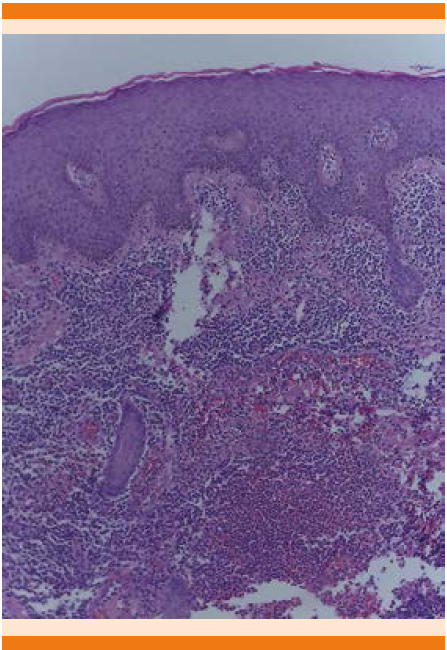

En el flanco derecho se palpó una masa blanda renitente de 8 cm de diámetro, no fija a planos profundos y no dolorosa (que correspondía a la hernia inguinal). Con diagnóstico clínico de micobacteriosis atípica vs tuberculosis cutánea se inició protocolo de estudio con biometría hemática, química sanguínea y pruebas de función hepática, que se encontraron en límites normales. Se obtuvo telerradiografía de tórax sin anormalidades. El derivado proteico purificado (PPD) fue negativo. La biopsia de piel demostró infiltrado granulomatoso, no tuberculoso crónico (Figura 3).

Figura 3 Microfotografía 4X H/E con atrofia epidérmica y papilomatosis e infiltrado inflamatorio granulomatoso crónico (caso 1).

1. La histología con tinción de hematoxilina y eosina que se caracteriza por un infiltrado granulomatoso con inflamación crónica, inespecífica y supurativa, donde difícilmente se observan granulomas de tipo tuberculoide, la histología de las lesiones puede ayudar, pero no es específica durante los tres primeros meses.14